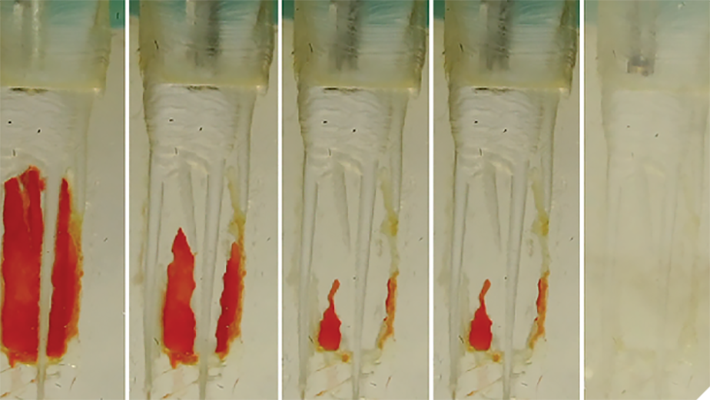

The most common odontogenic infection is that of the periapical tissues most frequently caused by dental caries, a deep restoration, or failed root canal treatment.1 Apical periodontitis (AP) has been found to have a prevalence of 50% in patients under the age of 50, and the prevalence and risk of AP has been found to be … Read more